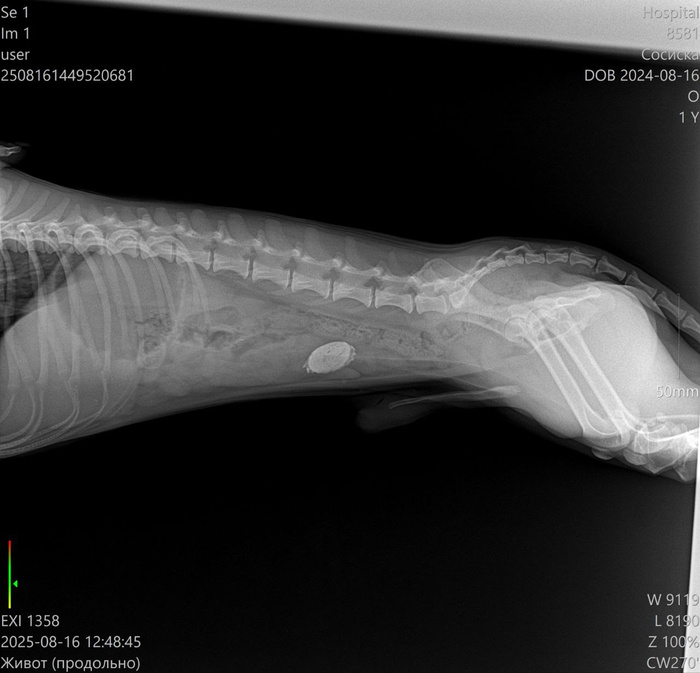

Краткое содержание для ЛЛ: такса сожрал какую-то пробку и через некоторое время у него начались проблемы. Спасибо ветеринарам: таксу - подкромсали, ненужное - убрали, нужное - оставили.

Ветеринарная клиника: измерение температуры, сделали УЗИ - в желудке обнаружена какая-то инородная штука, или показалось или... завтра на операцию.

Клизмы и прочие смазки не уговорили отдать то ли крышку, то ли ещё что-то такое металлическое.

Врачам пришлось резать сосиску и извлекать инородное тело.